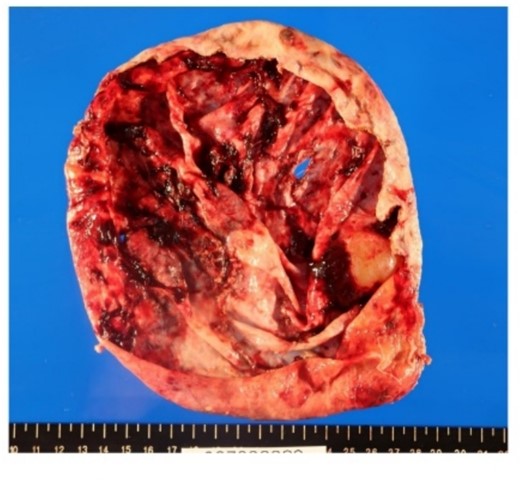

From these findings, we made the diagnosis of ruptured simple liver cyst and performed laparoscopic liver cyst fenestration and irrigation drainage 1 week after his admission to our hospital. A large hepatic cyst was found from the right abdomen to the right diaphragm. A dark red fluid suspected to be the content of the ruptured cyst was observed. We perforated the cyst capsule and 2500 ml of bloody fluid was drained. We resected the cystic wall as much as possible (Fig. 4). Postoperatively, paralytic ileus occurred but it was treated conservatively. The patient was transferred back to the previous hospital for the further treatment of the joint fracture on postoperative day 24.

Resection in the cystic wall, remaining 2 cm on the liver side was left.

Surgical specimen showed no neoplastic lesion (Fig. 5). Pathological diagnosis was a non-parasitic simple hepatic cyst with acute inflammation and hemorrhage. The cystic wall presented bile duct epithelium and liver lobules. Immunohistochemical staining showed that only CA19-9 was positive in the hepatic cyst wall epithelium (Fig. 6). The patient’s serum levels of CA19-9, CA125 and CEA were 164.0 U/mL, 126.3 U/mL, and 1.0 ng/mL, respectively, on postoperative day 23. A follow-up abdominal CT scan performed 2 months after the surgery did not show any sign of tumor.